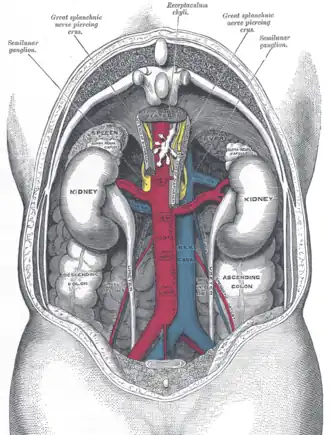

The relations of the viscera and large vessels of the abdomen.

The relations of the viscera and large vessels of the abdomen. -